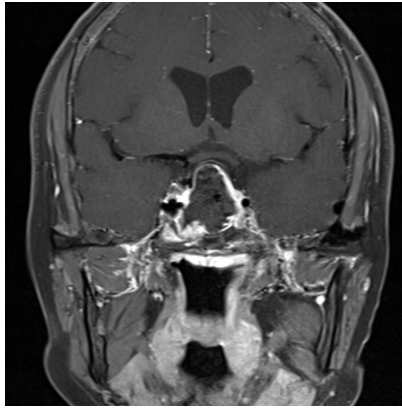

术后MR复查提示肿瘤近全切除

术后病理提示:促肾上腺皮质激素腺瘤